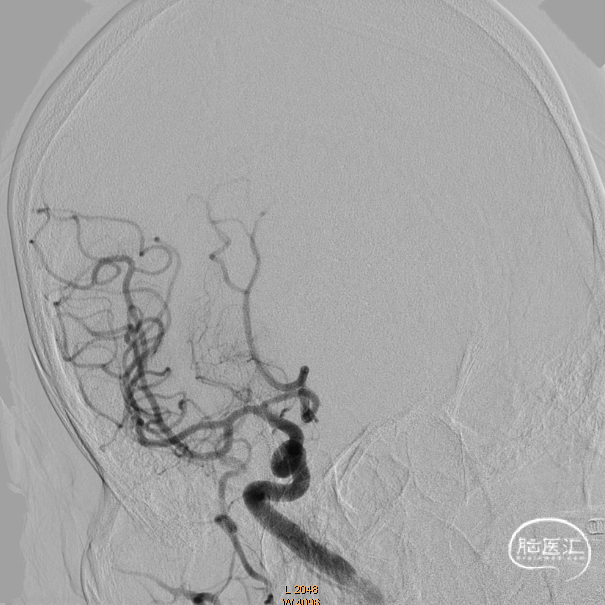

术前影像学资料

造影证实右侧颈内动脉闭塞。

左侧正侧位造影。

后循环造影。

微导管越过闭塞部位造影证实在真腔。

Syphonet®取栓支架到位,释放后等待5分钟使支架与血栓相互嵌合,可见支架显影清晰。

术后造影,一把三级再通。